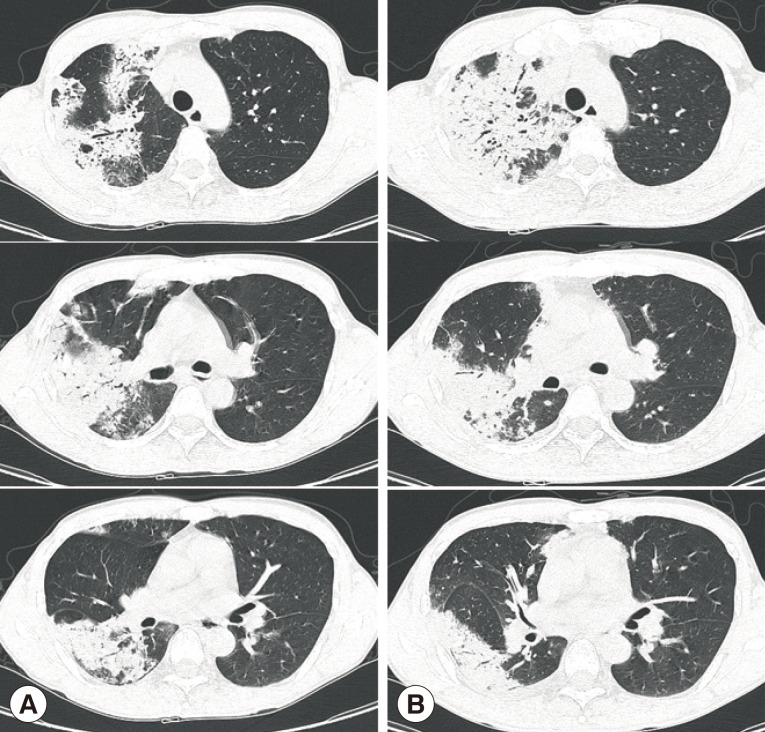

Chest X-ray and computed tomography (CT) showed large consolidations in the right upper lobe, middle lobe, and lower lobe superior segments (

Fig. 1A,

2A). Bronchoalveolar lavage (BAL) was performed through the right upper and lower superior segmental bronchi. Microbiological investigation of the sputum and BAL fluid for bacteria, mycobacteria (Ziehl-Neelsen stain, culture, and PCR), and fungi were all negative. Only

Aspergillus serum antigen (galactomannan assay) was positive with a value of 0.76 (optical density cutoff value, ≥0.5). With a diagnosis of probable invasive aspergillosis, considering the patient's immune status and positive galactomannan assay, amphotericin B (1.0 mg/kg/day) was administered for 8 days. However, the patient's symptoms worsened, and the chest CT findings showed deterioration (

Fig. 2B).

Fig. 2Chest computed tomography scans in the lung window setting showing large consolidations in the right upper lobe, middle lobe, and lower lobe superior segment at initial presentation (A) and increased extent on the 9th day after hospitalization (B).